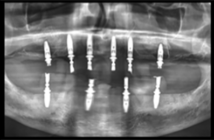

En outre, Romexis 7 associe de manière automatique les images CBCT et les scans intraoraux. Il optimise également la planification implantaire en générant automatiquement des propositions de plan implantaire. Le logiciel sélectionne de façon intelligente la taille de l’implant et le positionne de façon à ce qu’il s’adapte à l’anatomie du patient, laissant le soin aux dentistes de vérifier le plan et de poursuivre la création du guide implantaire, qui est également simplifiée. Romexis identifie automatiquement la zone convenant au guide chirurgical en se basant sur le plan implantaire et les scans correspondants. En résumé, ces fonctionnalités basées sur l’IA permettent d’optimiser le flux de travail quotidien des cabinets dentaires qui ont ainsi plus de temps à consacrer aux soins de leurs patients.